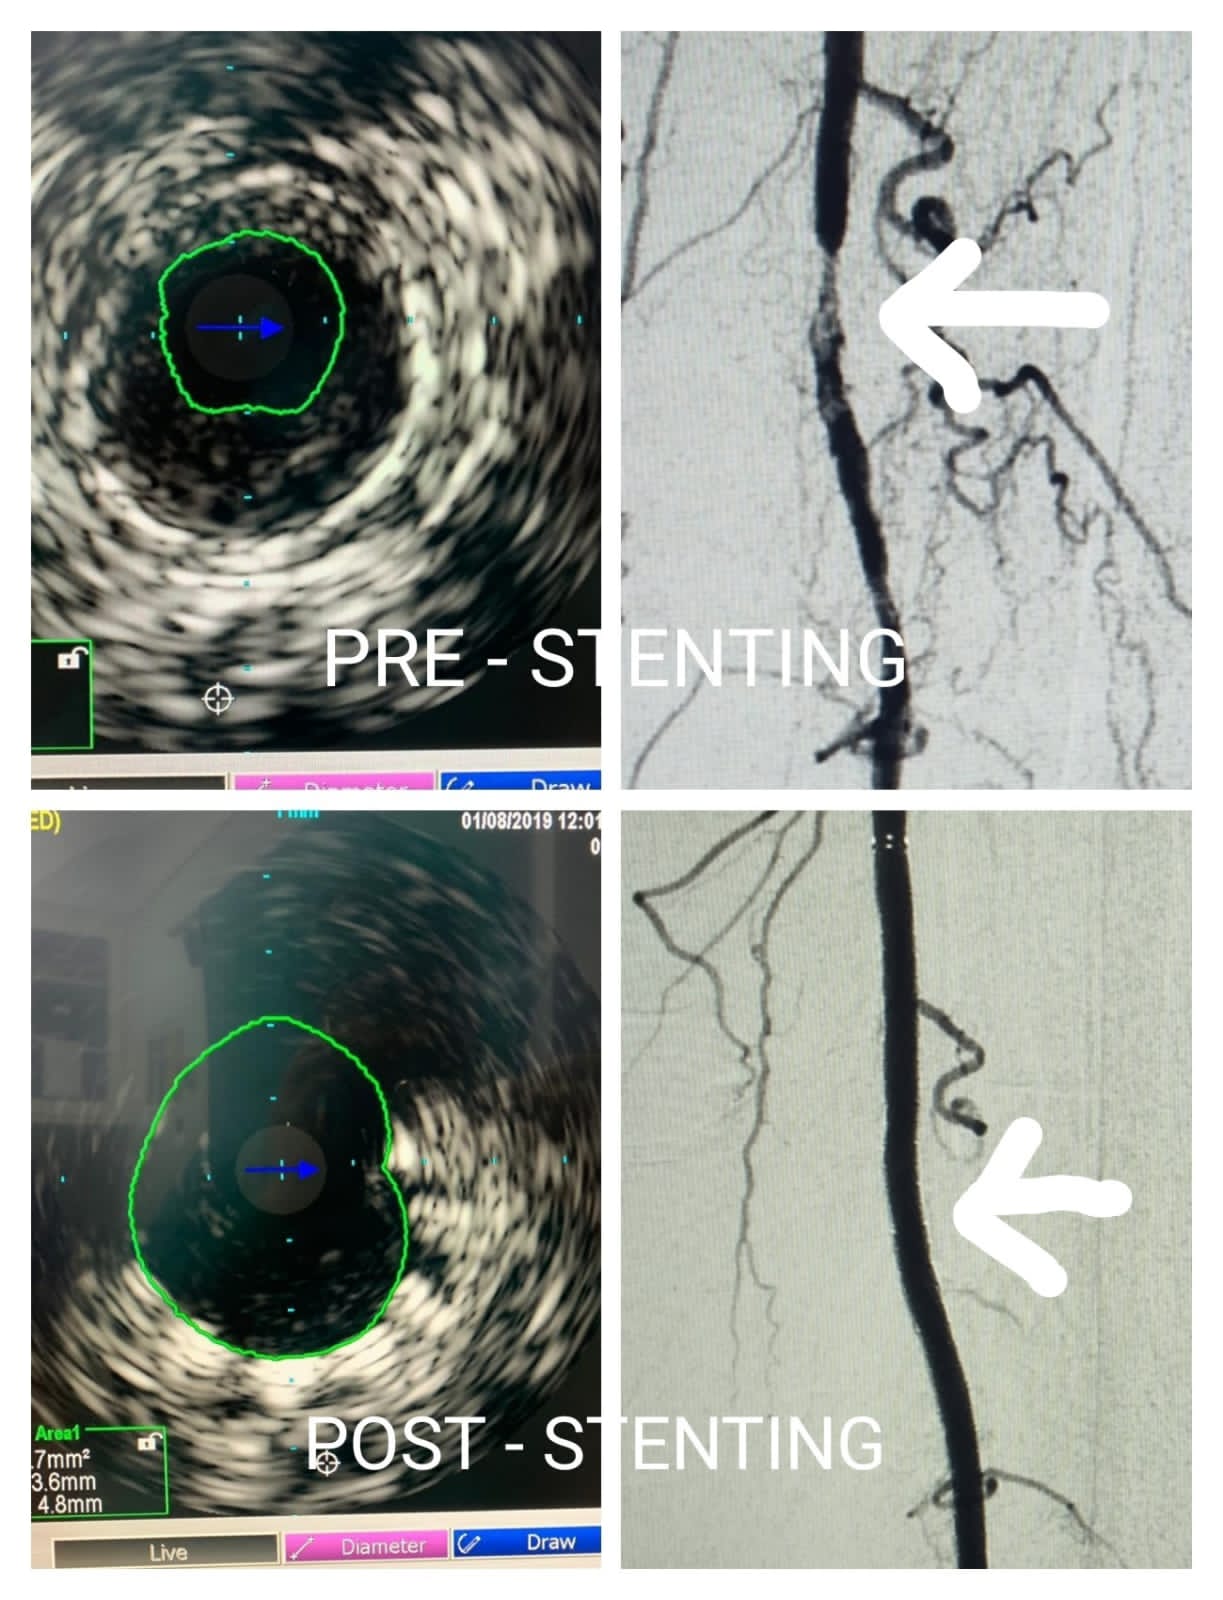

Carotid Artery Stenting Procedure Pre procedure - 95% stenosis in Internal Carotid Artery Post Procedure- Deploy Stent & restore complete blood flow

Performed Intravascular ultrasound (IVUS)